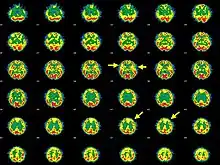

| Brain SPECT transaxial images of a patient afflicted with Hashimoto's encephalopathy. | |

- Single photon emission computed tomography shows focal and global hypoperfusion (75% of cases)